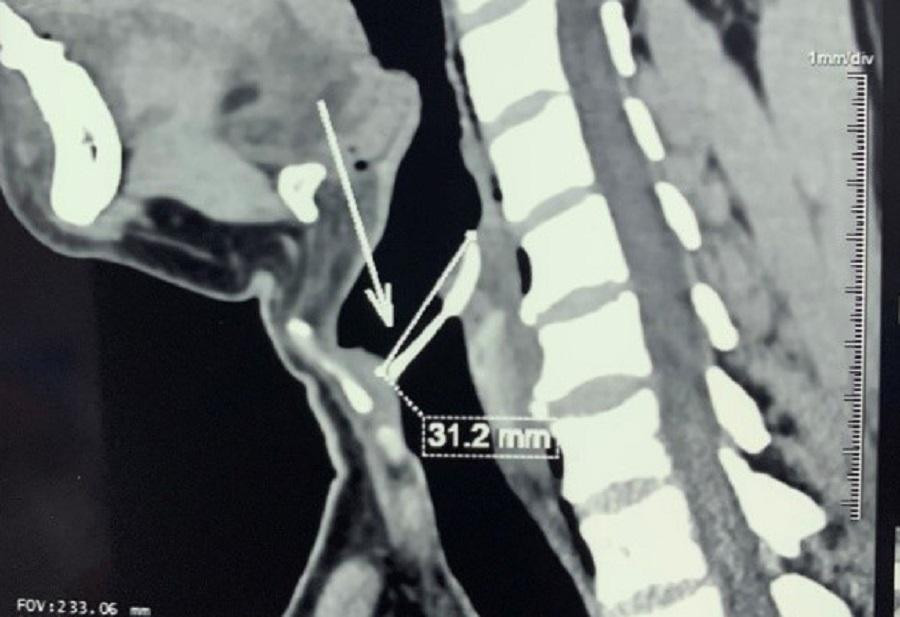

| Chiếc xương cá dài hơn 3 cm ghim vào thanh quản của bệnh nhân sau khi hóc sặc |

Tại đây, qua thăm khám, nội soi hạ họng thanh quản cho bệnh nhân, bác sĩ phát hiện dị vật đã ghim chặt ở thanh môn. Bệnh nhân được chụp CT-scan vùng cổ và ngực thì phát hiện, chiếc xương cá ghim vào dây thanh và sụn phễu, tràn khí vùng kế cận, rách niêm mạc xoang. Bên cạnh đó, người bệnh còn tình cờ phát hiện rối loạn dung nạp đường huyết qua các xét nghiệm sinh hóa máu.